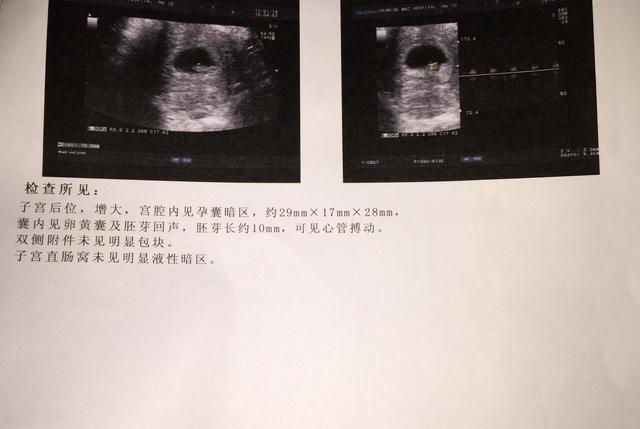

胎囊 , 也叫孕囊 , 是胚胎的最初形状 , 受精卵着床之后不断发育 , 生成原始的胎盘组织 , 被羊膜、血管网包裹的那一小团胚胎就叫做胎囊 , 胎儿的生长就是在这里开始的 。

孕前月经规律 , 月经周期28-30天的女性 , 在孕35天左右 , 通过B超就可以看到胎囊的存在 , 到了孕6周左右 , 胎囊大约有2厘米大;孕10周左右 , 胎囊大约有5厘米 , 到了孕11周左右 , 胎囊则会逐渐消失 。

正常情况下 , 胎囊会在子宫的宫底、前壁、后壁、上部或者是中间 , 大多数时候它们会是比较规律、且边缘清晰的圆形或者椭圆形 , 如果出现形状不规则或者边缘模糊 , 且在子宫下部 , 则有可能会发生流产 。